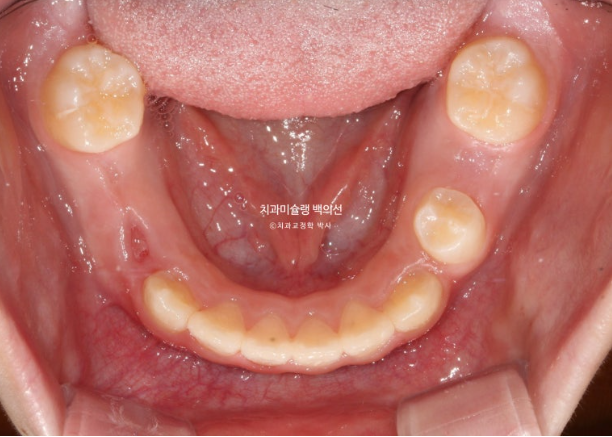

어금니 반대교합은 상악 악궁이 좁아서 생기는 문제입니다.

즉 악궁확장이 필요하고 인비절라인 퍼스트로 악궁확장을 동반하여 MA (mandible advance, 하악전진기능) 기능을 이용한 비대칭 치료가 필요합니다.

어금니 반대교합의 원인은 좁은 상악 악궁에 있습니다.

이제 인비절라인퍼스트 치료로 악궁확장, 앞니배열 등을 먼저 진행하여 교합간섭 해소를 도모합니다.

악궁확장을 통해 어금니 반대교합은 해소되었고 앞니배열은 좋아졌습니다.

나중에 영구치 송곳니 날 공간도 충분히 마련되었습니다.